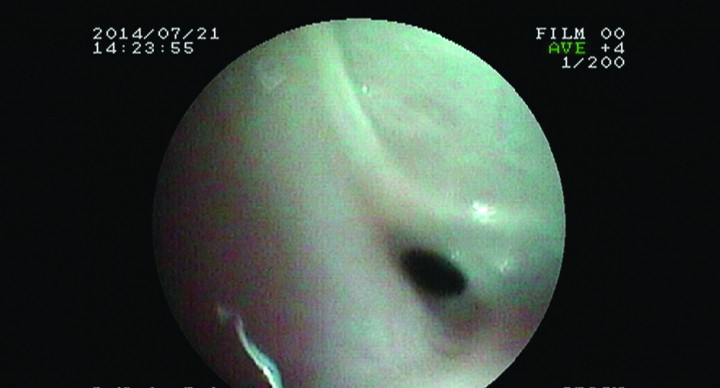

Se procede a anestesiar al paciente para valorar la realización de cirugía del paladar blando y, si procede, realizar una rinoscopia y endoscopia en retroflexión para confirmar que no exista otra patología. Se premedica con dexmedetomidina 0,01 mg/kg i.m., midazolam 0,1 mg/kg i.m. y metadona 0,2 mg/kg i.m., se induce con propofol a dosis de 1 mg/kg (dosis-efecto), la intubación y el mantenimiento, con isoflurano y oxígeno. Una vez comprobado que el paladar no colapsa la vía aérea, se procede a realizar una rinoscopia rostral con endoscopio rígido (Fig. 4) y una endoscopia con endoscopio flexible Fujinon EVE 200-EPX 2200 (4,9 mm de diámetro externo y 600 mm de longitud) para valorar la nasofaringe (Fig. 5). Se visualiza que la fosa nasal izquierda es macroscópicamente normal y sin presencia de moco; la fosa nasal derecha presenta cornetes más finos y angulosos de lo normal compatibles con el padecimiento de un proceso nasal antiguo severo. Tampoco se observa mucosidad. Con el endoscopio flexible se observa una estenosis nasofaríngea casi completa por una membrana que deja un orificio de 1 mm aproximadamente (Fig. 6), localizada muy caudal, cerca del borde caudal del paladar blando en posición excéntrica.

<p>Imagen endoscópica del estrechamiento por membrana a nivel de nasofaringe.</p>

Imagen endoscópica del estrechamiento por membrana a nivel de nasofaringe.